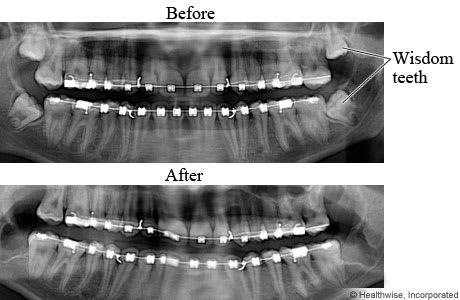

Wisdom Teeth X-ray | Cigna

www.cigna.comX-ray Oral Image With An Inflamed Wisdom Tooth Close-up Stock Photo

www.cigna.comX-ray Oral Image With An Inflamed Wisdom Tooth Close-up Stock Photo